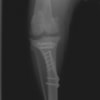

・術後レントゲン

手術前TPA 28.4° が術後TPA 11.7° に矯正されました。

術前TPA計測

術後TPA計測

Fixin T字プレート使用して固定

検査結果から前十字靱帯の断裂を疑い脛骨高平部水平化骨切り術(TPLO)を実施することに。また、パテラの安定化のために縫工筋内側広筋切開、滑車溝形成術も併せて実施。